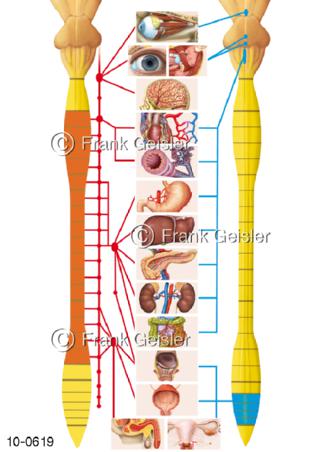

Bildergalerie Nervensystem

Bilder zum Nervensystem,dem Gehirn, Teil des zentralen Nervensystem, Zentralnervensystem ZNSmit Rückenmark, Abbildungen zum Nervengeflecht (Nervenplexus), die Verflechtungen von Nervenfasern, aus der Wirbelsäule hervortretende Nervenäst sowie Nervenzellen der Nerven